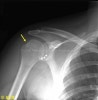

X-ray : 힐삭스 병변(Hill-Sachs lesion)

추가적으로 힐삭스 병변을 보기 위한 Stryker notch view, 관절와 전하방 골성 병변을 보기 위한 West point view, apical oblique view 등을 시행할 수 있습니다.

어깨 전방 탈구는 대부분 간접 외상에 의하며 젊은 연령의 급성 외상성 전방탈구에서는 대부분 Bankart lesion 또는 관절낭의 파열이 존재하며 관절와 전방연에 상완골이 압착되어 상완골두 후측방 부위에서 압박 골절이 동반될 수 있습니다(Hill-Sachs lesion).